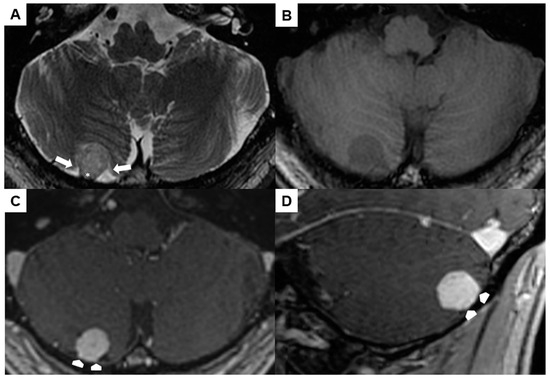

| Our second case | 52 | M | Extra-axial infratentorial on the right | Asymptomatic | No | 1.5 months | No recurrence at 5 months, No neurological deficits |